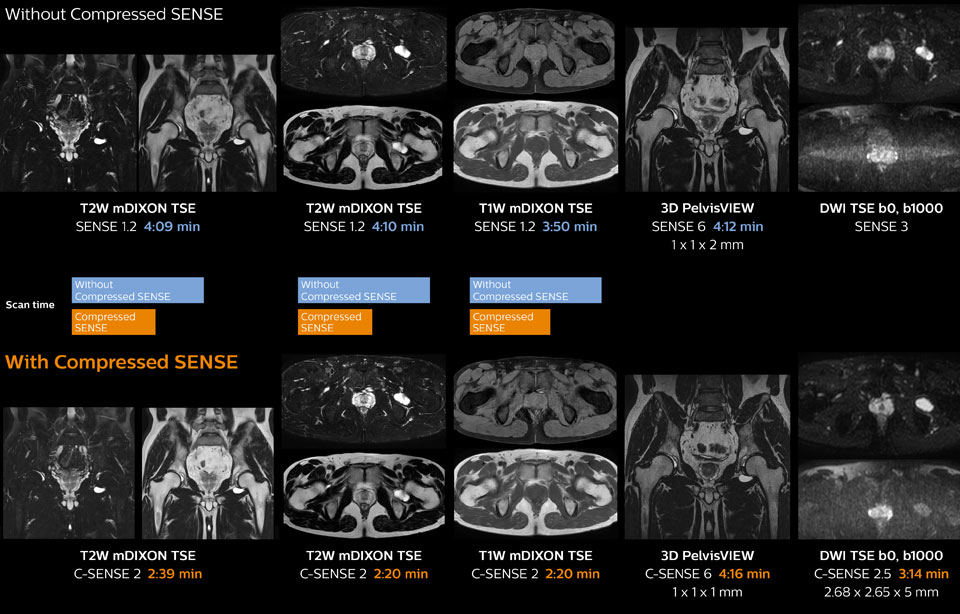

Ingenia 1.5T MRI scans with and without Compressed SENSE are compared for this case of a hip with a synovial cyst. In the mDIXON sequence, the Compressed SENSE factor used is higher than the SENSE factor on the previous scan, so scan times are reduced without sacrificing image quality. The high resolution images are useful for diagnosing of a detailed dissection. The diffusion TSE with Compressed SENSE shows reduced noise compared to the Diffusion TSE with SENSE and the artifact has disappeared.

So in this case, Compressed SENSE helped in reducing scan times of the examination. The Compressed SENSE images allowed the radiologist to confidently diagnose the lesion and see the anatomic relationships of the abnormal signal to the surrounding structures.

In this MRI exam of pelvis in a patient with myoma, Compressed SENSE is used to accelerate individual sequences and thus the entire examination on Ingenia 1.5T. Compressed SENSE allowed for a decrease in scan time for the T2 TSE from 3:38 to 1:46 minutes. The Compressed SENSE images in this case show fewer motion artifacts than the images from the previous protocol with SENSE. In 3D PelvisVIEW, the Compressed SENSE images have a higher and isotropic spatial resolution with a scan time similar to the SENSE sequence. The improved spatial resolution and better contrast in the myometrium of the uterus allowed radiologist Dr. Koyama to confidently diagnose the cancerous lesion in the uterus. The use of Compressed SENSE accelerates scanning times and increases spatial resolution in 3D PelvisVIEW.